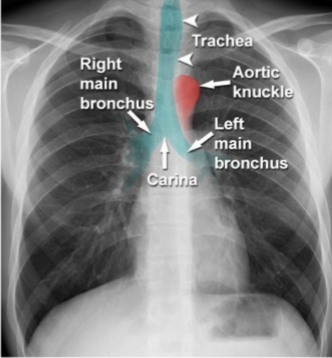

Label this CXR (10 things)

1) trachea 2) hilum- should have R and L 3) lungs 4) diaphragm 5) heart 6) aortic knuckle 7) ribs 8) scapulae 9) breasts 10) bowel gas

Identify trachei, bronchi, aortic nuckle

yes